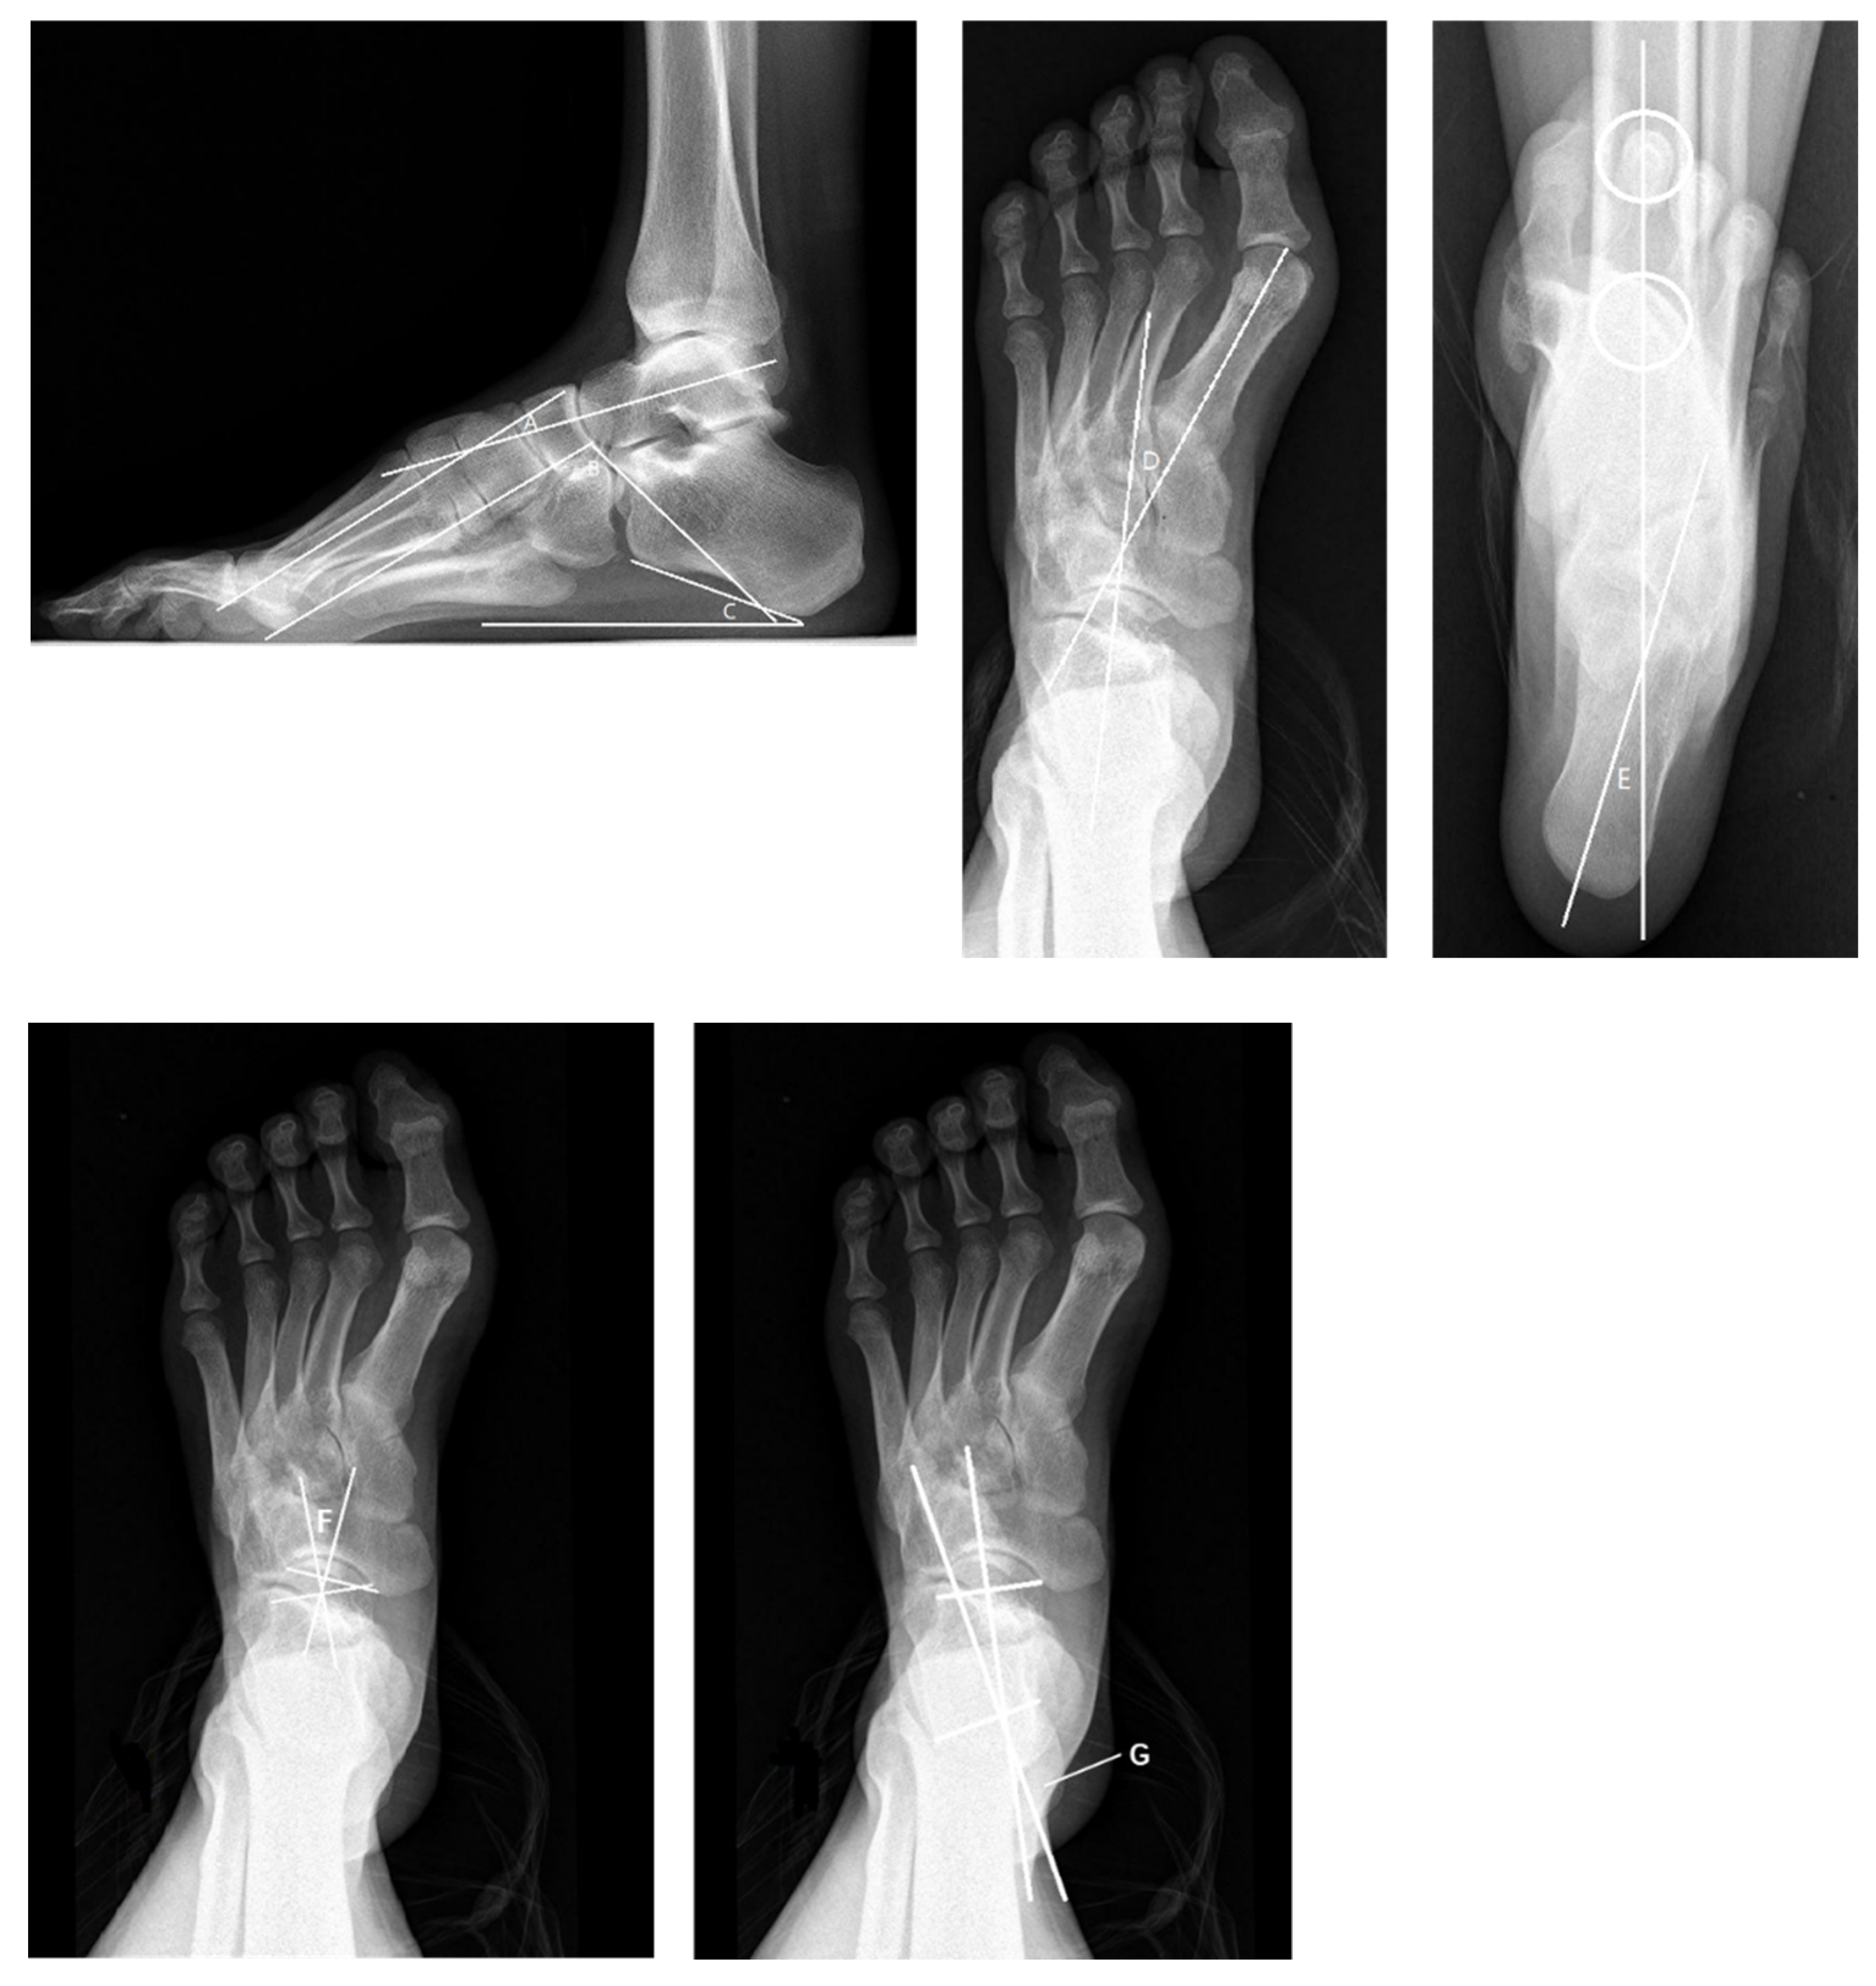

Radiological evaluation should be emphasized, as simple radiographs can aid considerably in operative decision making [34,35]. Radiographs should be taken with the patient’s weight-bearing on the foot and ankle so as to allow for the assessment of the true deformity. Radiographs of the foot including anteroposterior (AP), oblique, and lateral views are important to identify the apex of the deformity, the latter in particular. On the AP view we may observe a decreased AP–talo–first metatarsal (TM1) angle and TC (talo-calcaneal) angle. On the lateral view, an increased lateral talo–first metatarsal (Meary) angle, decreased talar declination, increased calcaneal pitch (Pitch) angle, and a decreased lateral talo-calcaneal (Djian–Annonier) angle may be seen. The apex of the deformity is always proximal to the base of the first metatarsal, either at the first tarsometatarsal (TMT) joint, the cuneiform, the naviculocuneiform (NC), or the talonavicular (TN) joint. In addition, AP, mortise, and lateral views of the ankle should be obtained to identify whether arthritis or varus exists. The long axial X-ray of the calcaneus allows for the assessment of the hindfoot alignment in the coronal plane, which is usually the varus in cavus foot. The tibial calcaneal angle (TCA) may be increased (Figure 7). The full-length X-ray of lower limbs in weight-bearing is taken to evaluate the alignment of the lower extremities and observe the presence of knock knee or tibial rotation. The radiological evaluation of cavus foot should also include the Coleman block test in order to assess the flexibility of the foot. In the recent literature, Dr. Michalski [36] and Dr. Tonya An [37] have conducted high quality research about bone morphology changes in cavus foot. Their research results indicate that the TN coverage angle (Figure 7) plays an important role in evaluating the effect of cavus foot correction.

Figure 7.

The radiological evaluation of cavus foot pre-operation. A: Meary Angle (−4°~4°) *. B: Djian–Annonier Angle (120°~130°) * C: Pitch Angle (20°~30°) * D: TM1 Angle (0°~20°) * E: TCA Angle (0°~5°) *. F: TN Coverage Angle (1.8°~19.3° male 6.7°~21.7° female) *. G: TC Angle (15°~35°) *. * Represent the normal range.